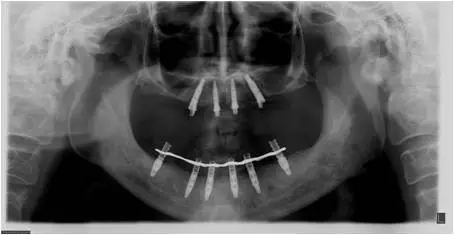

10個月后出現(xiàn)左上頜咬合痛,X線檢查發(fā)現(xiàn)上頜左側(cè)前磨牙區(qū)傾斜種植體周圍低密度影,臨床檢查種植體松動,其余種植體骨結(jié)合良好,遂拔除該種植體(圖3-4)。愈合3個月,CBCT片顯示:25區(qū)種植窩空虛(圖5),愈合不佳,26區(qū)竇底剩余骨高度不足2mm(圖6),其余種植體骨愈合良好,15區(qū)傾斜種植體邊緣骨疑似吸收至第三螺紋(結(jié)合全景片)?;颊咭蠊潭ㄐ迯?fù)。

圖3

圖4